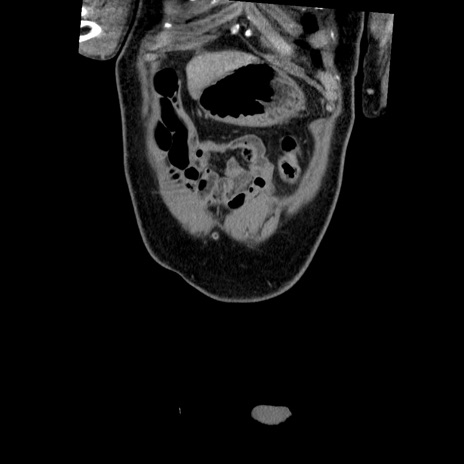

横断像

【症例】50歳代男性

【主訴】腹痛

【現病歴】AVMからの被殻出血のため回復期リハ病棟入院中。 本日午後3時頃急に下腹部痛が出現した。

【既往歴】AVM、被殻出血、虫垂炎、高血圧

【身体所見】意識晴明、左半身不全麻痺、会話の理解は良好、36.5°C、腹部:膨隆、全体に板状硬、下腹部正中に圧痛点あり、反跳痛-、筋性防御不明、右下腹部にope scar

【データ】WBC 9400、CRP 0.06